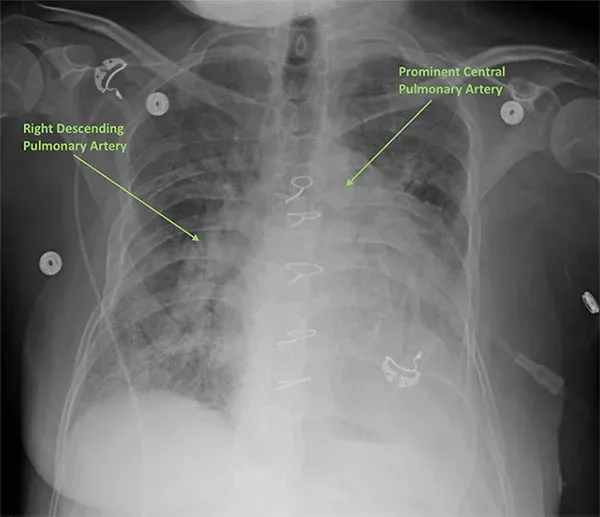

Image showing the heart and Pulmonary Hypertension

How pulmonary hypertension is diagnosed clinically